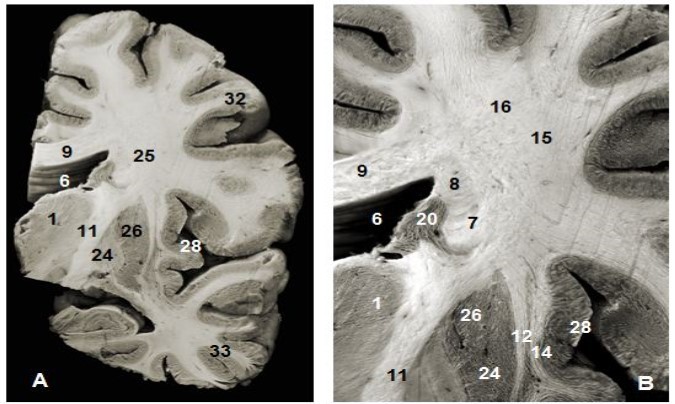

Figure 1.(A) Coronal view of the left hemisphere and (B) global view after magnification and before dissection of (A). 1. Thalamus, 6. Lateral ventricule 7. Subependymal substratum, 9. Corpus callosum, 11. Internal capsule, 12. External capsule, 13. Claustrum, 14. Extreme capsule, 16. Upper branch of the SLF , 20. Head of caudeus nucleus, 23. Putamen, 24. Globus pallidus, 25. Lower branch of SLF 28. Insula, 30. Corona radiata, 32. Parietal pole, 33. Temporal pole.

Anterior and superior thalamocortical pathways course obliquely and connect anterior, mediodorsal, lateral ventral anterior, lateral dorsal and lateral posterior thalamic nuclei to the cerebral cortex. They exposed after the removal of the head and body of the corpus callosum were . A coronal view of the thalamus confirms the course of these fibers to the thalamus. The sub-ependymal stratum and gray matter are medial to the thalamic radiations (Figure 1). The successive excision of the insular cortex, claustrum, fibers of the extreme capsule, the putamen and globus pallidus and pyramidal tract exposed other components lateral to the internal capsule (Figure 1, Figure 4). Fibers of the extreme and external capsules and of the lenticular nucleus (putamen and globus pallidus) formed an inferior relationship with the stem of the uncinate and the inferior occipitofrontal fasciculi. A coronal section through the cerebral hemisphere and the thalamus completed the study of thalamic radiations. The optic radiations and the ventral amygdaloid tract which loop through the anterior perforated substance and the lateral expansion of the anterior commissure sheathed by the Gratiolet canal, which were not include intentionally in our illustrations, were further away. Gratiolet optic radiations connect the thalamus to the geniculate body and the posterior nucleus of the occipital cortex. These thalamic radiations line up the lateral ventricle.

The abscission of the frontal, parietal and temporal opercula exposed the superior longitudinal fasciculus (SLF) which was the first hemispheric and the largest association bundle to be seen and is located medial to the insular cortex. The SLF is an arcuate fasciculus which wraps around the insula and connects the frontal, parietal, occipital and temporal lobes together (Figure 1, Figure 3). It has a superior and an inferior surface, anterior or frontal end, posterior extremity and the lateral and medial margins. The lateral opercular border is flattened and more spread across. Its fibers project to the straight gyrus which was exposed after the withdrawal of the insular arcuate fibers. The medial edge is in contact with the corona radiata. The frontal, parietal and temporal opercula are lateral to the SLF. Ablation of the lenticular nucleus exposed the inferior and medial aspect of the SLF. Superiorly, U-shaped fibers are 13mm away from the cortex at the level of the central sulcus. The anterior extremity is lateral to the fanning end of the uncinate and inferior occipitofrontal fasciculi, then the corona radiata and the frontal horn of the lateral ventricle. This anterior end was lateral to the ventricle and 19,6mm away from the cortex (10-25mm). The posterior extremity was separated from the lateral ventricle by the optic radiations and the tapetum of the corpus callosum.

The sub-ependymal stratum also known as the subcallosal stratum was made of a fiber-free layer of white matter. This layer of white matter was exposed after excision of the ependymal layer lining the ventricular system. It is located between the caudate nucleus and callosal radiations (Figure 1, Figure 2, Figure 4). Under the ependyma backward to the occipital horns, callosal fibers form together the tapetum and thalamic radiations. Our dissection failed to show a precise boundary between the tapetum and the sub-ependymal stratum. The substratum is a sub-ependymal structure located between the caudate nucleus, the corpus callosum radiations and the internal capsule. Globally, it is located below the ependyma and medial to the cingulum. It is not made of fibers connecting the frontal and the occipital lobes.